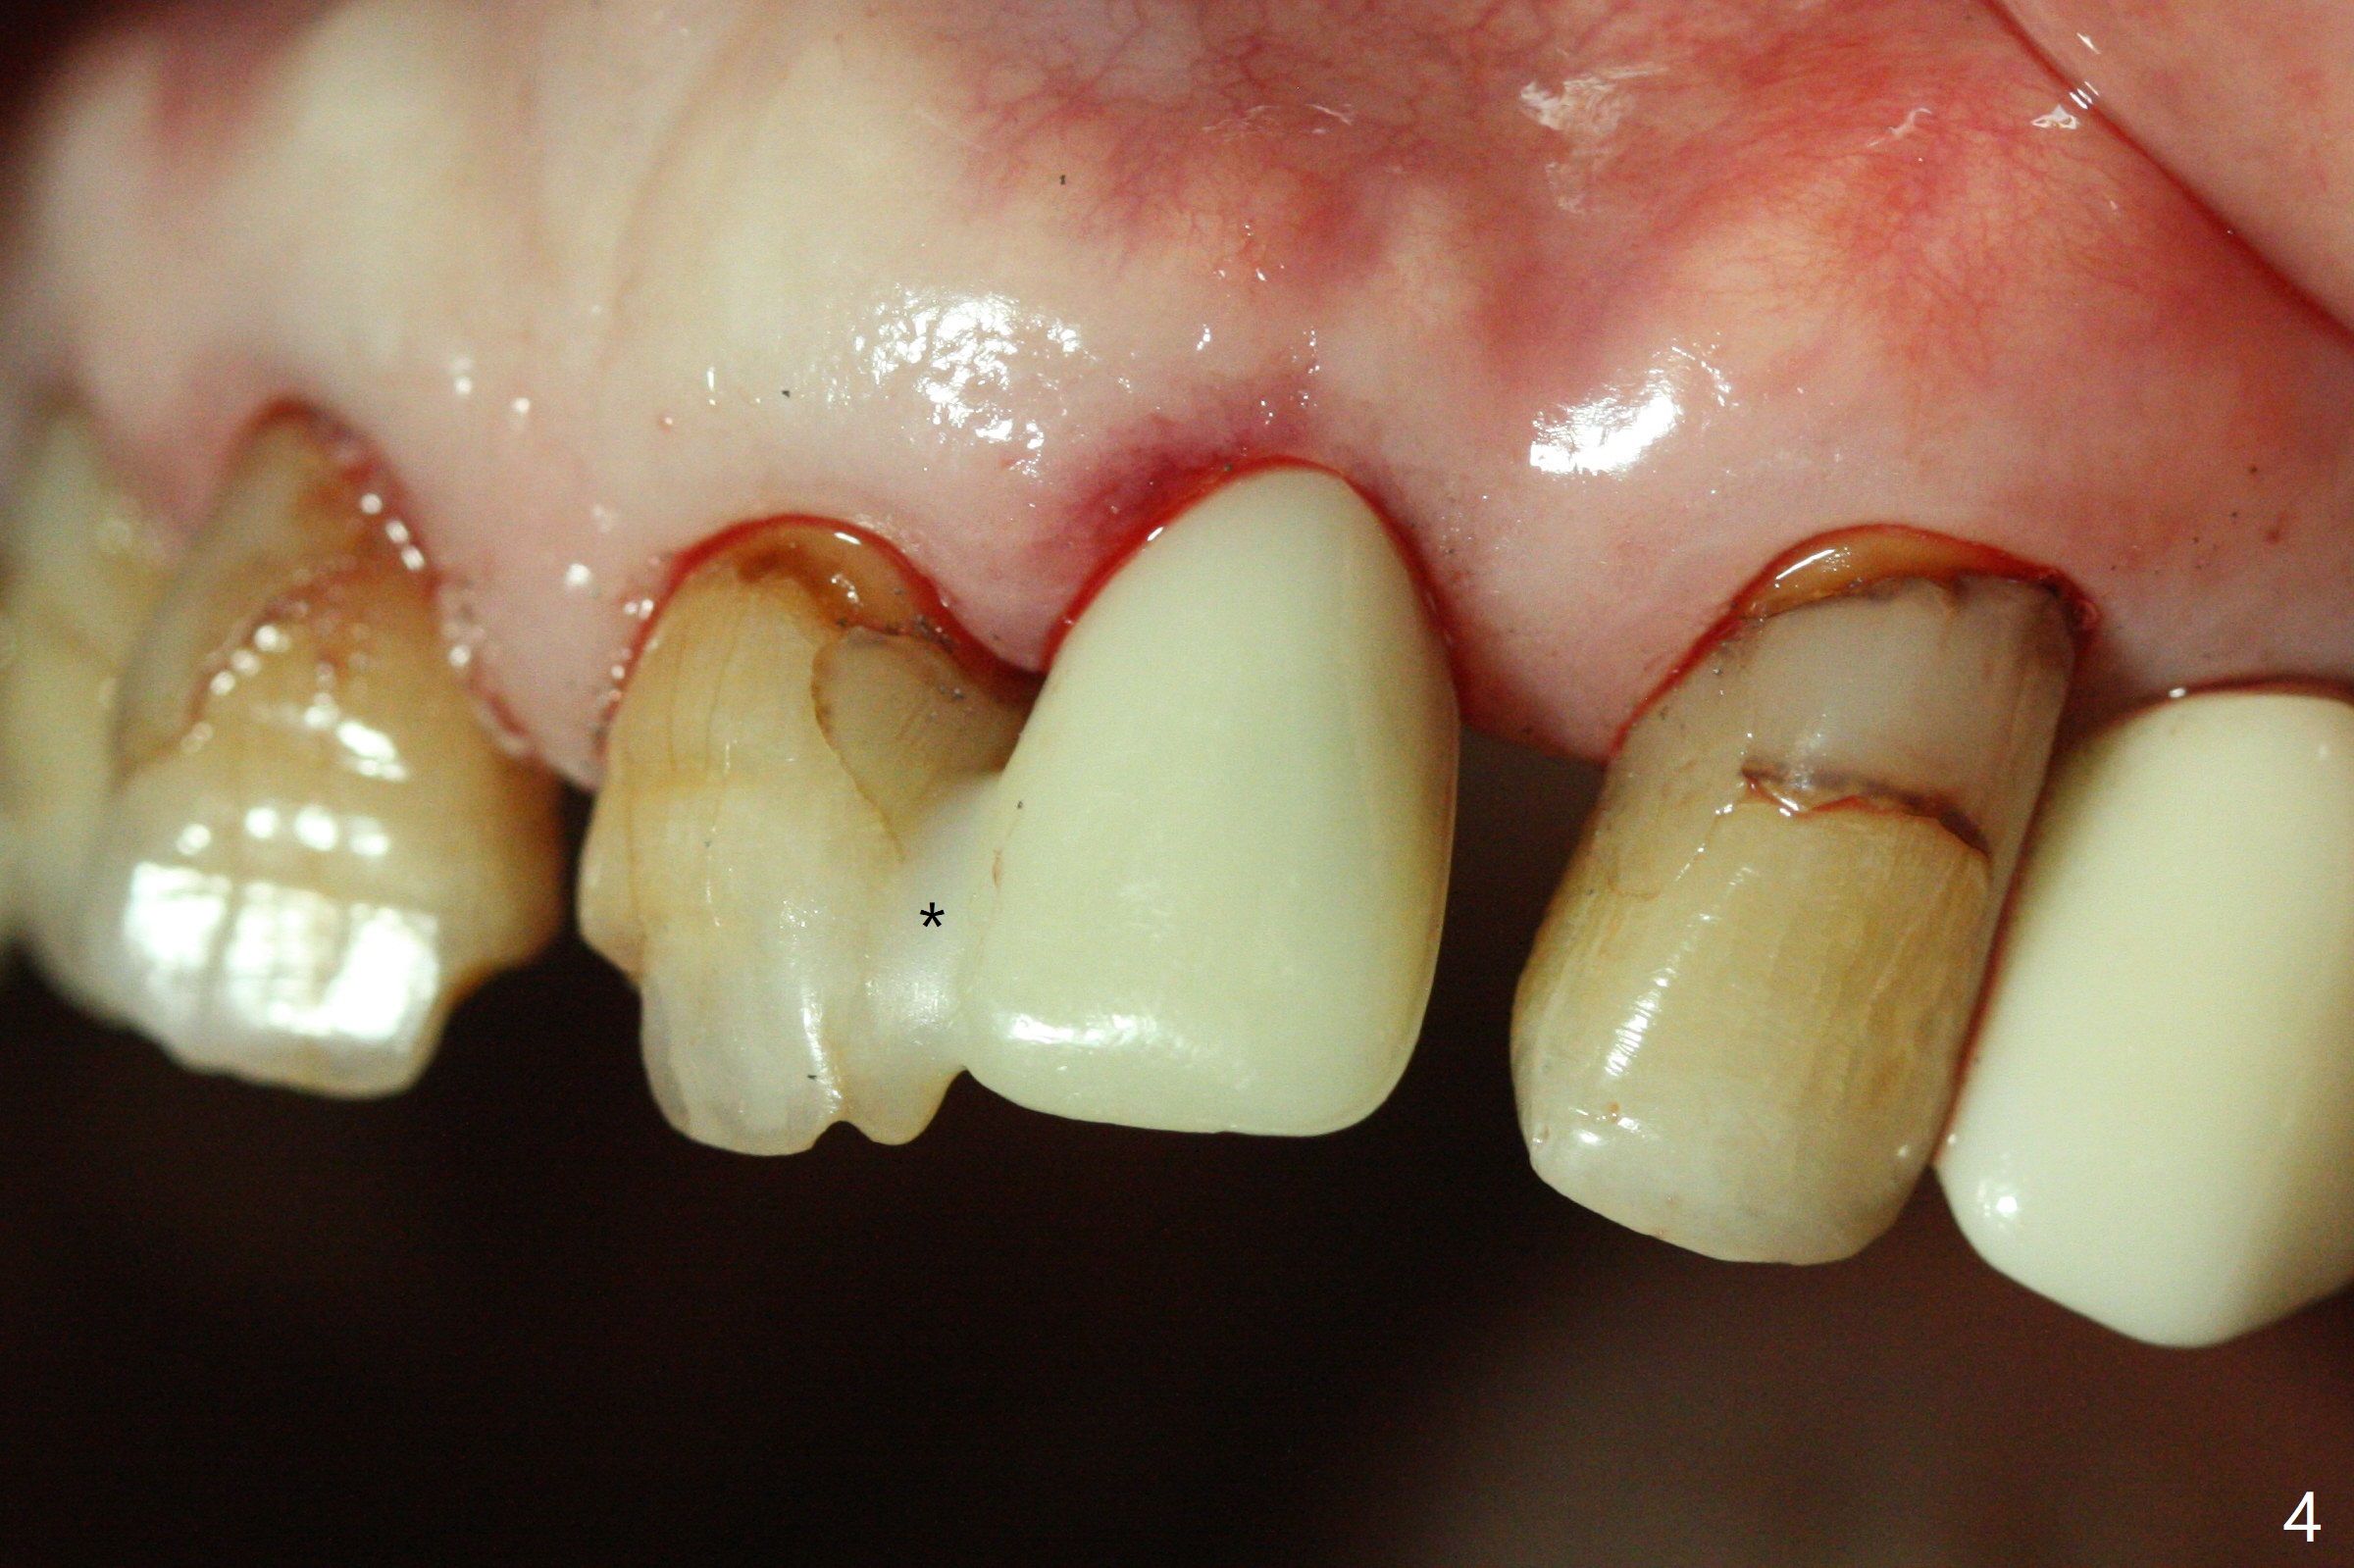

After undersized drilling in depth at #10 (2.2x13 mm (10.5 mm offset), Fig.1), a 2.5x13 mm 1-piece implant is placed (Fig.2,3), as compared to the design (Fig.3'). Following 3 more turns of the implant (~ 20 Ncm), bone graft and heavy buccal reduction of the coronal end of the abutment, an immediate provisional is bonded to the tooth #9 (Fig.4) and splinted to the tooth #11 with a twisted wire (Fig.5). To increase stability and reduce reduction, a 3 mm 1-piece implant could be used with 15 degree abutment. The implant remains stable 5 months postop (Fig.6). The implant seems to be flexible before heavy occlusal reduction; note the periimplant micro-space (Fig.7). The patient is a bruxer. The implant crown seems to be minimally mobile 2 months post cementation (Fig.8, without treatment). 牙冠粘固后1年1个月软硬组织正常(图九)。